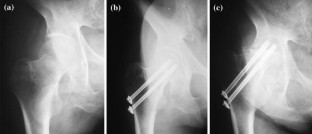

Fig. 2